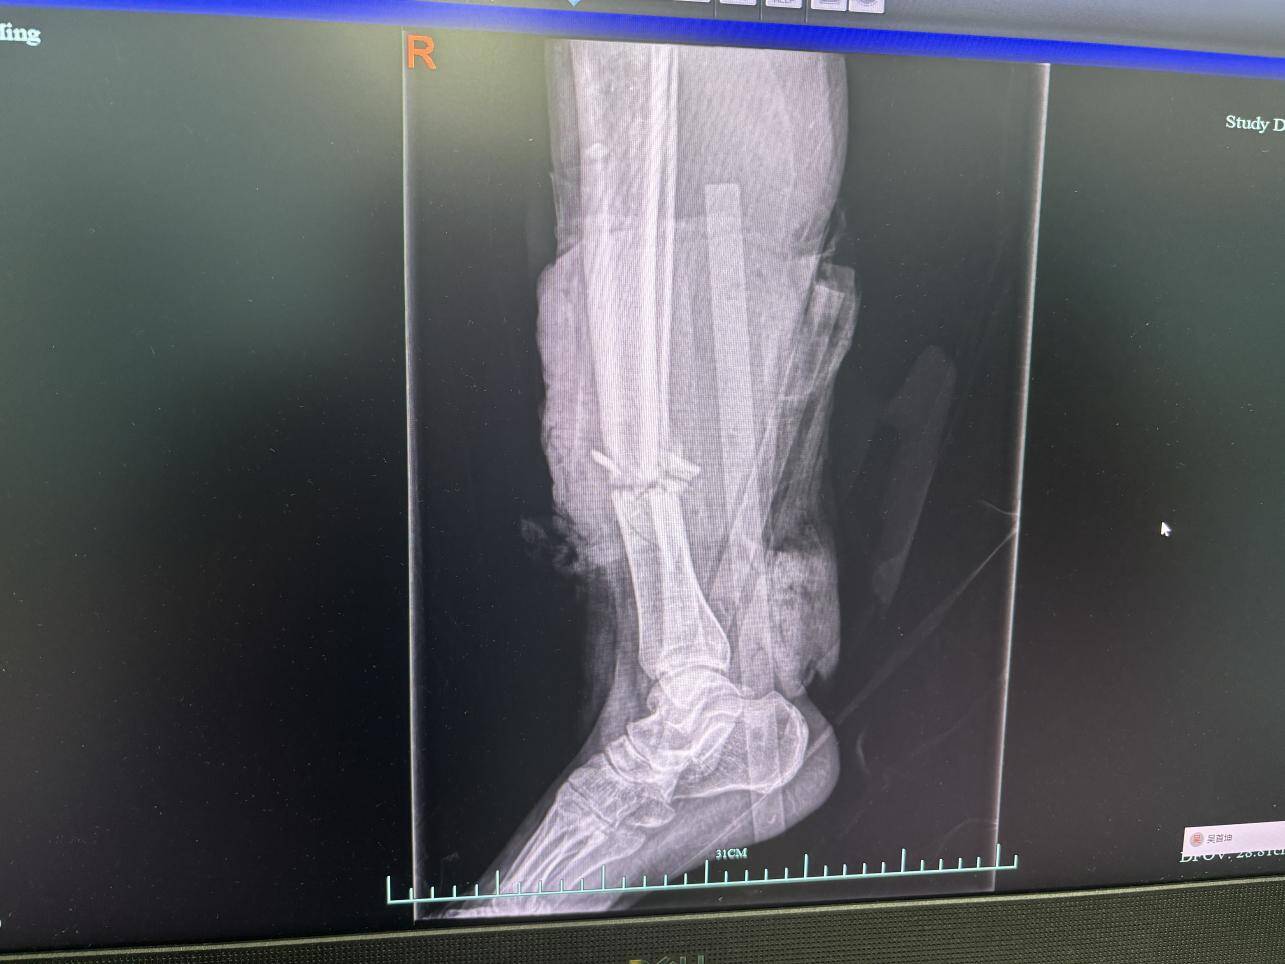

上月初,55岁的老张在工地作业时,没躲过迎面而来的铲车,右下肢被狠狠撞中。送到浙大四院急诊时,小腿横截面血肉模糊,几乎快断了!伤口触目惊心,骨头断裂、缺损、暴露,皮肤组织大面积缺损,伤口里还裹着泥沙。

更让人揪心的是,足趾已泛白,没什么活性,足背动脉跳得极弱,这意味着下肢血液循环已经严重“断供”,再拖下去,腿可能就保不住了。

“这属于典型的高能量创伤导致的开放性骨折。”该院骨科副主任医师李钧团队紧急会诊后,一句话点出了病情的严重性。这类损伤不仅是骨头断裂,还伴随血管、神经、肌肉等多重软组织损伤,若处理不当,感染、骨髓炎甚至截肢的风险极高,治疗周期长且难度大。

收治当天小腿情况